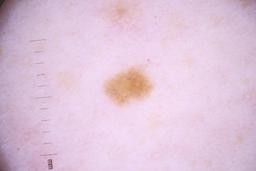

ISIC_4077341

- Challenge 2020: Training

- IP_1969685 IL_9238622

Clinical

| Field | Value |

|---|---|

| acquisition_day | 1 |

| age_approx | 50 |

| anatom_site_1 | Trunk |

| anatom_site_2 | Anterior trunk |

| concomitant_biopsy | False |

| dermoscopic_type | contact non-polarized |

| diagnosis_1 | Benign |

| diagnosis_confirm_type | serial imaging showing no change |

| family_hx_mm | False |

| image_type | dermoscopic |

| lesion_id | IL_9238622 |

| patient_id | IP_1969685 |

| personal_hx_mm | True |

| sex | male |